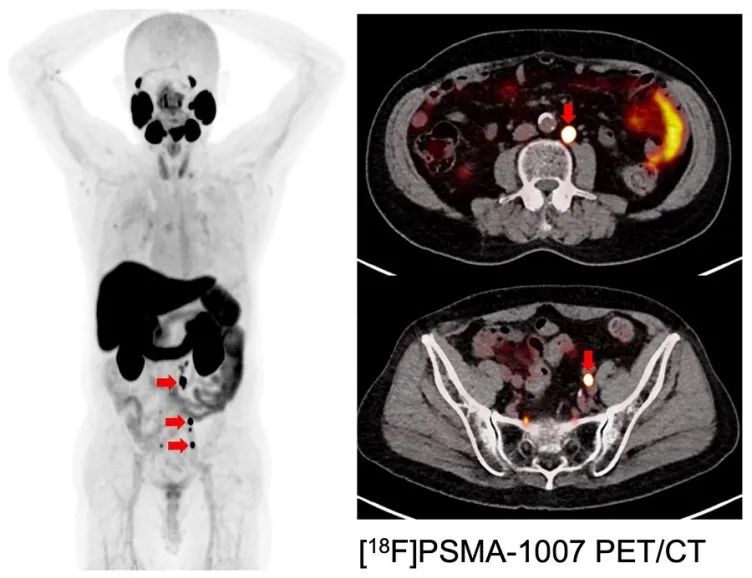

(图2)靶向PSMA的PET图像:内分泌治疗耐药的前列腺癌,有多个淋巴结转移(红色箭头)。

大阪大学与德国杜塞尔多夫大学的联合研究中,一直在开展针对PSMA的PET诊断成像的临床研究(图2)。此外,使用β射线核素镥(Lu-177)的PSMA治疗在海外引起了人们的关注,但是Lu-177目前还不能在日本国内生产,并且有患者对Lu-177 抵抗。而砹是一种能发射比传统放射线能量更高的α射线的核素,即使对β射线治疗有抵抗性的人也可能有效。理化研究所(RIKEN)利用重离子加速器设施RI Beam Factory的加速器,开发出本研究所需砹原料的量产技术,并稳定供应给大阪大学。